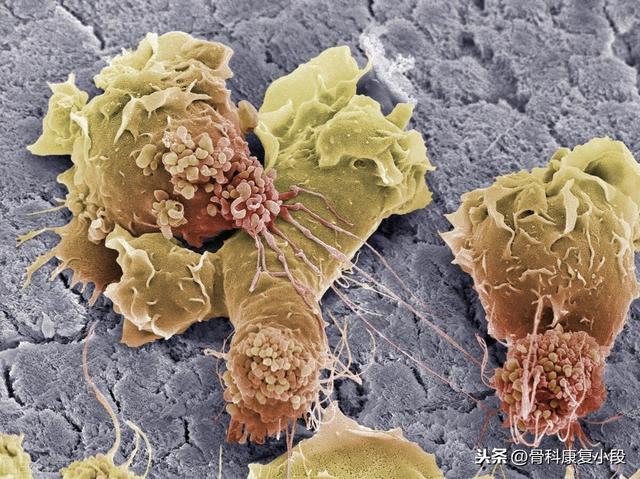

métastases osseusessont des tumeurs malignes qui prennent naissance à l'extérieur du tissu osseux.Transféré par la circulation sanguine vers le tissu osseux.Maladies causées par des lésions osseuses et dont la principale manifestation est la douleur.

Par exemple, si un patient souffre d'un cancer du poumon, le cancer du poumon se forme d'abord dans le tissu pulmonaire, mais le tissu pulmonaire n'a pas la capacité d'absorber le cancer du poumon.Les cellules tumorales dans le poumon peuvent être séparées de la masse d'origineIl s'agit d'un état dans lequel la circulation sanguine pénètre dans d'autres parties du corps, par exemple dans les os, ce qui est appelémétastases osseusesLe point important est que même si des cellules cancéreuses sont trouvées dans les os, elles sont toujours là. Le point important ici est que même si des cellules cancéreuses sont trouvées dans les os, lesLes cellules cancéreuses ne proviennent pas du tissu osseux, mais des poumons.。

Métastase osseuse, également appelée tumeur osseuse métastatique. Il s'agit d'un cancer métastatique des os qui se forme lorsqu'une tumeur maligne provenant d'organes ou de tissus extérieurs à l'os se métastase dans l'os par le sang ou la lymphe et continue à se développer.